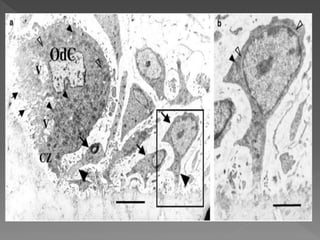

 The cell organelles of an osteoclast consists of

• #65 The odontoclast in the lacuna exhibits a developed ruffled border (small arrows), a clear zone (CZ), abundant vacuoles (V) and mitochondria (small arrowheads), and scattered rER (open arrowheads), which indicate that this odontoclast is activated for root resorption. Mononuclear cells (arrows) close to the odontoclast-detached surface are extending cytoplasmic processes (arrowheads) toward the root surface.